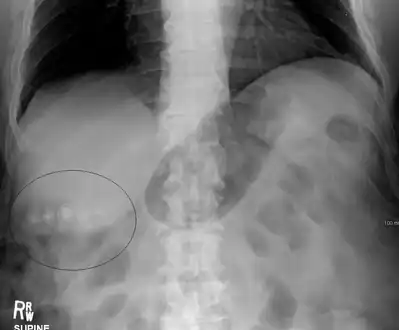

Gallstones as seen on plain X-ray

Mixed (brown pigment stones) typically contain 20–80% cholesterol (or 30–70%, according to the Japanese classification system).[36] Other common constituents are calcium carbonate, palmitate phosphate, bilirubin and other bile pigments (calcium bilirubinate, calcium palmitate and calcium stearate). Because of their calcium content, they are often radiographically visible. They typically arise secondary to infection of the biliary tract which results in the release of β-glucuronidase (by injured hepatocytes and bacteria) which hydrolyzes bilirubin glucuronides and increases the amount of unconjugated bilirubin in bile. Between 4% and 20% of stones are mixed.[3]